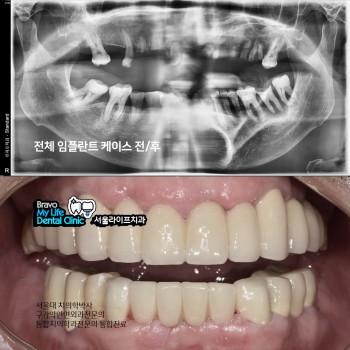

전체 임플란트 수술 케이스 전/후 사진

의학박사 김신근원장

보건복지부인증 구강악안면외과전문의